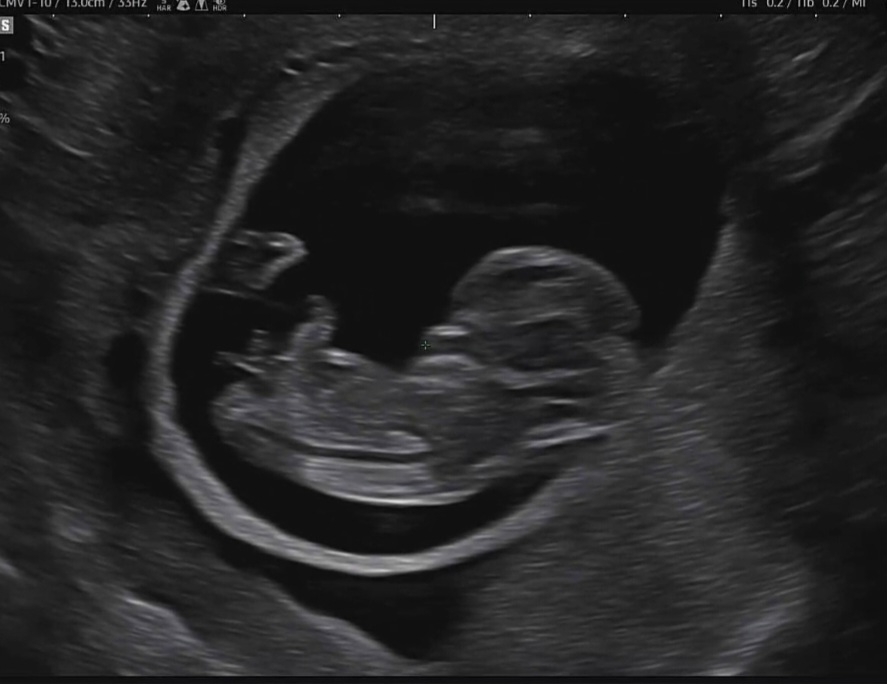

11주차 아기 각도법

11주차에 찍은 초음파인데 아기 각도법으로 성별유추가능할까요 ?? 너무궁금하네요 ㅠㅠㅠㅠ